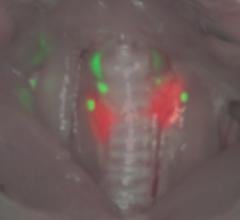

Researchers funded by the National Institute of Biomedical Imaging and Bioengineering (NIBIB) have developed two near-infrared (NIR) contrast agents that are efficiently taken up by the thyroid and parathyroid glands following intravenous injection. The researchers tested the contrast agents in rats and pigs and showed that they could be used to help distinguish the thyroid and parathyroid glands from surrounding tissue and from each other. Their findings appeared in the Jan. 5, 2015, issue of Nature Medicine.